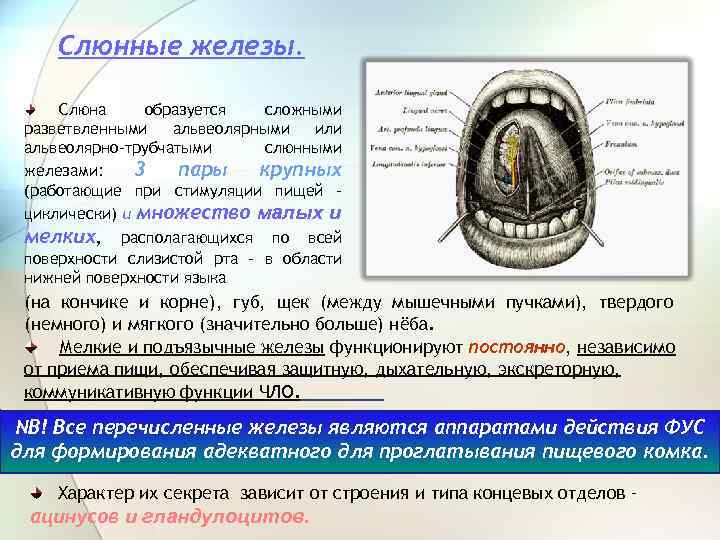

Слюнные железы. Слюна образуется сложными разветвленными альвеолярными или альвеолярно-трубчатыми слюнными железами: 3 пары крупных (работающие при стимуляции пищей циклически) и множество малых и мелких, располагающихся по всей поверхности слизистой рта - в области нижней поверхности языка (на кончике и корне), губ, щек (между мышечными пучками), твердого (немного) и мягкого (значительно больше) нёба. Мелкие и подъязычные железы функционируют постоянно, независимо от приема пищи, обеспечивая защитную, дыхательную, экскреторную, коммуникативную функции ЧЛО. NB! Все перечисленные железы являются аппаратами действия ФУС для формирования адекватного для проглатывания пищевого комка. Характер их секрета зависит от строения и типа концевых отделов – ацинусов и гландулоцитов.